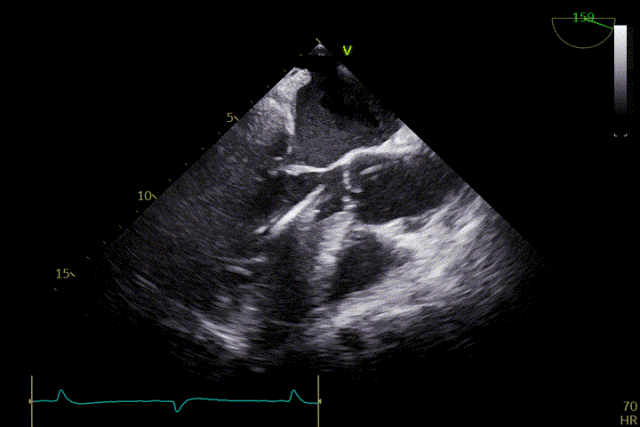

術后效果

患者主動脈瓣重度反流糾正,術后無反流、無瓣周漏。術后心臟彩超顯示人工生物瓣啟閉良好,平均跨瓣壓差2mmHg,流速正常。患者恢復情況良好,心功能較術前有了明顯改善。